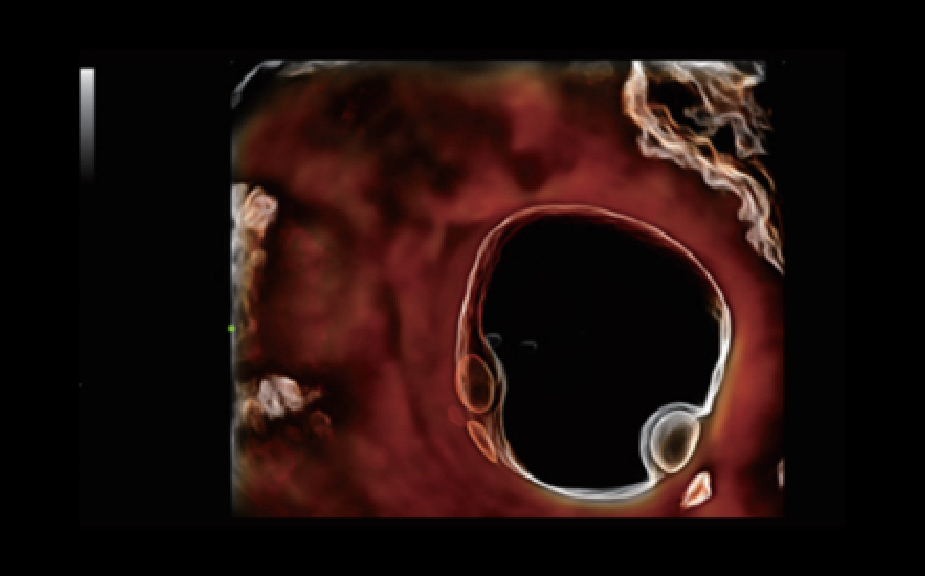

Nuewa I9? ??? ???? ?? ??? ?? ??? ???? ?? ??? ???? ???? ??? ?????. ??? ??? ??? ?? ????? ?? ???? ???? ???? ???? ??? ???? ??? ??? ???? ??? ???? ??? ?? ?????.